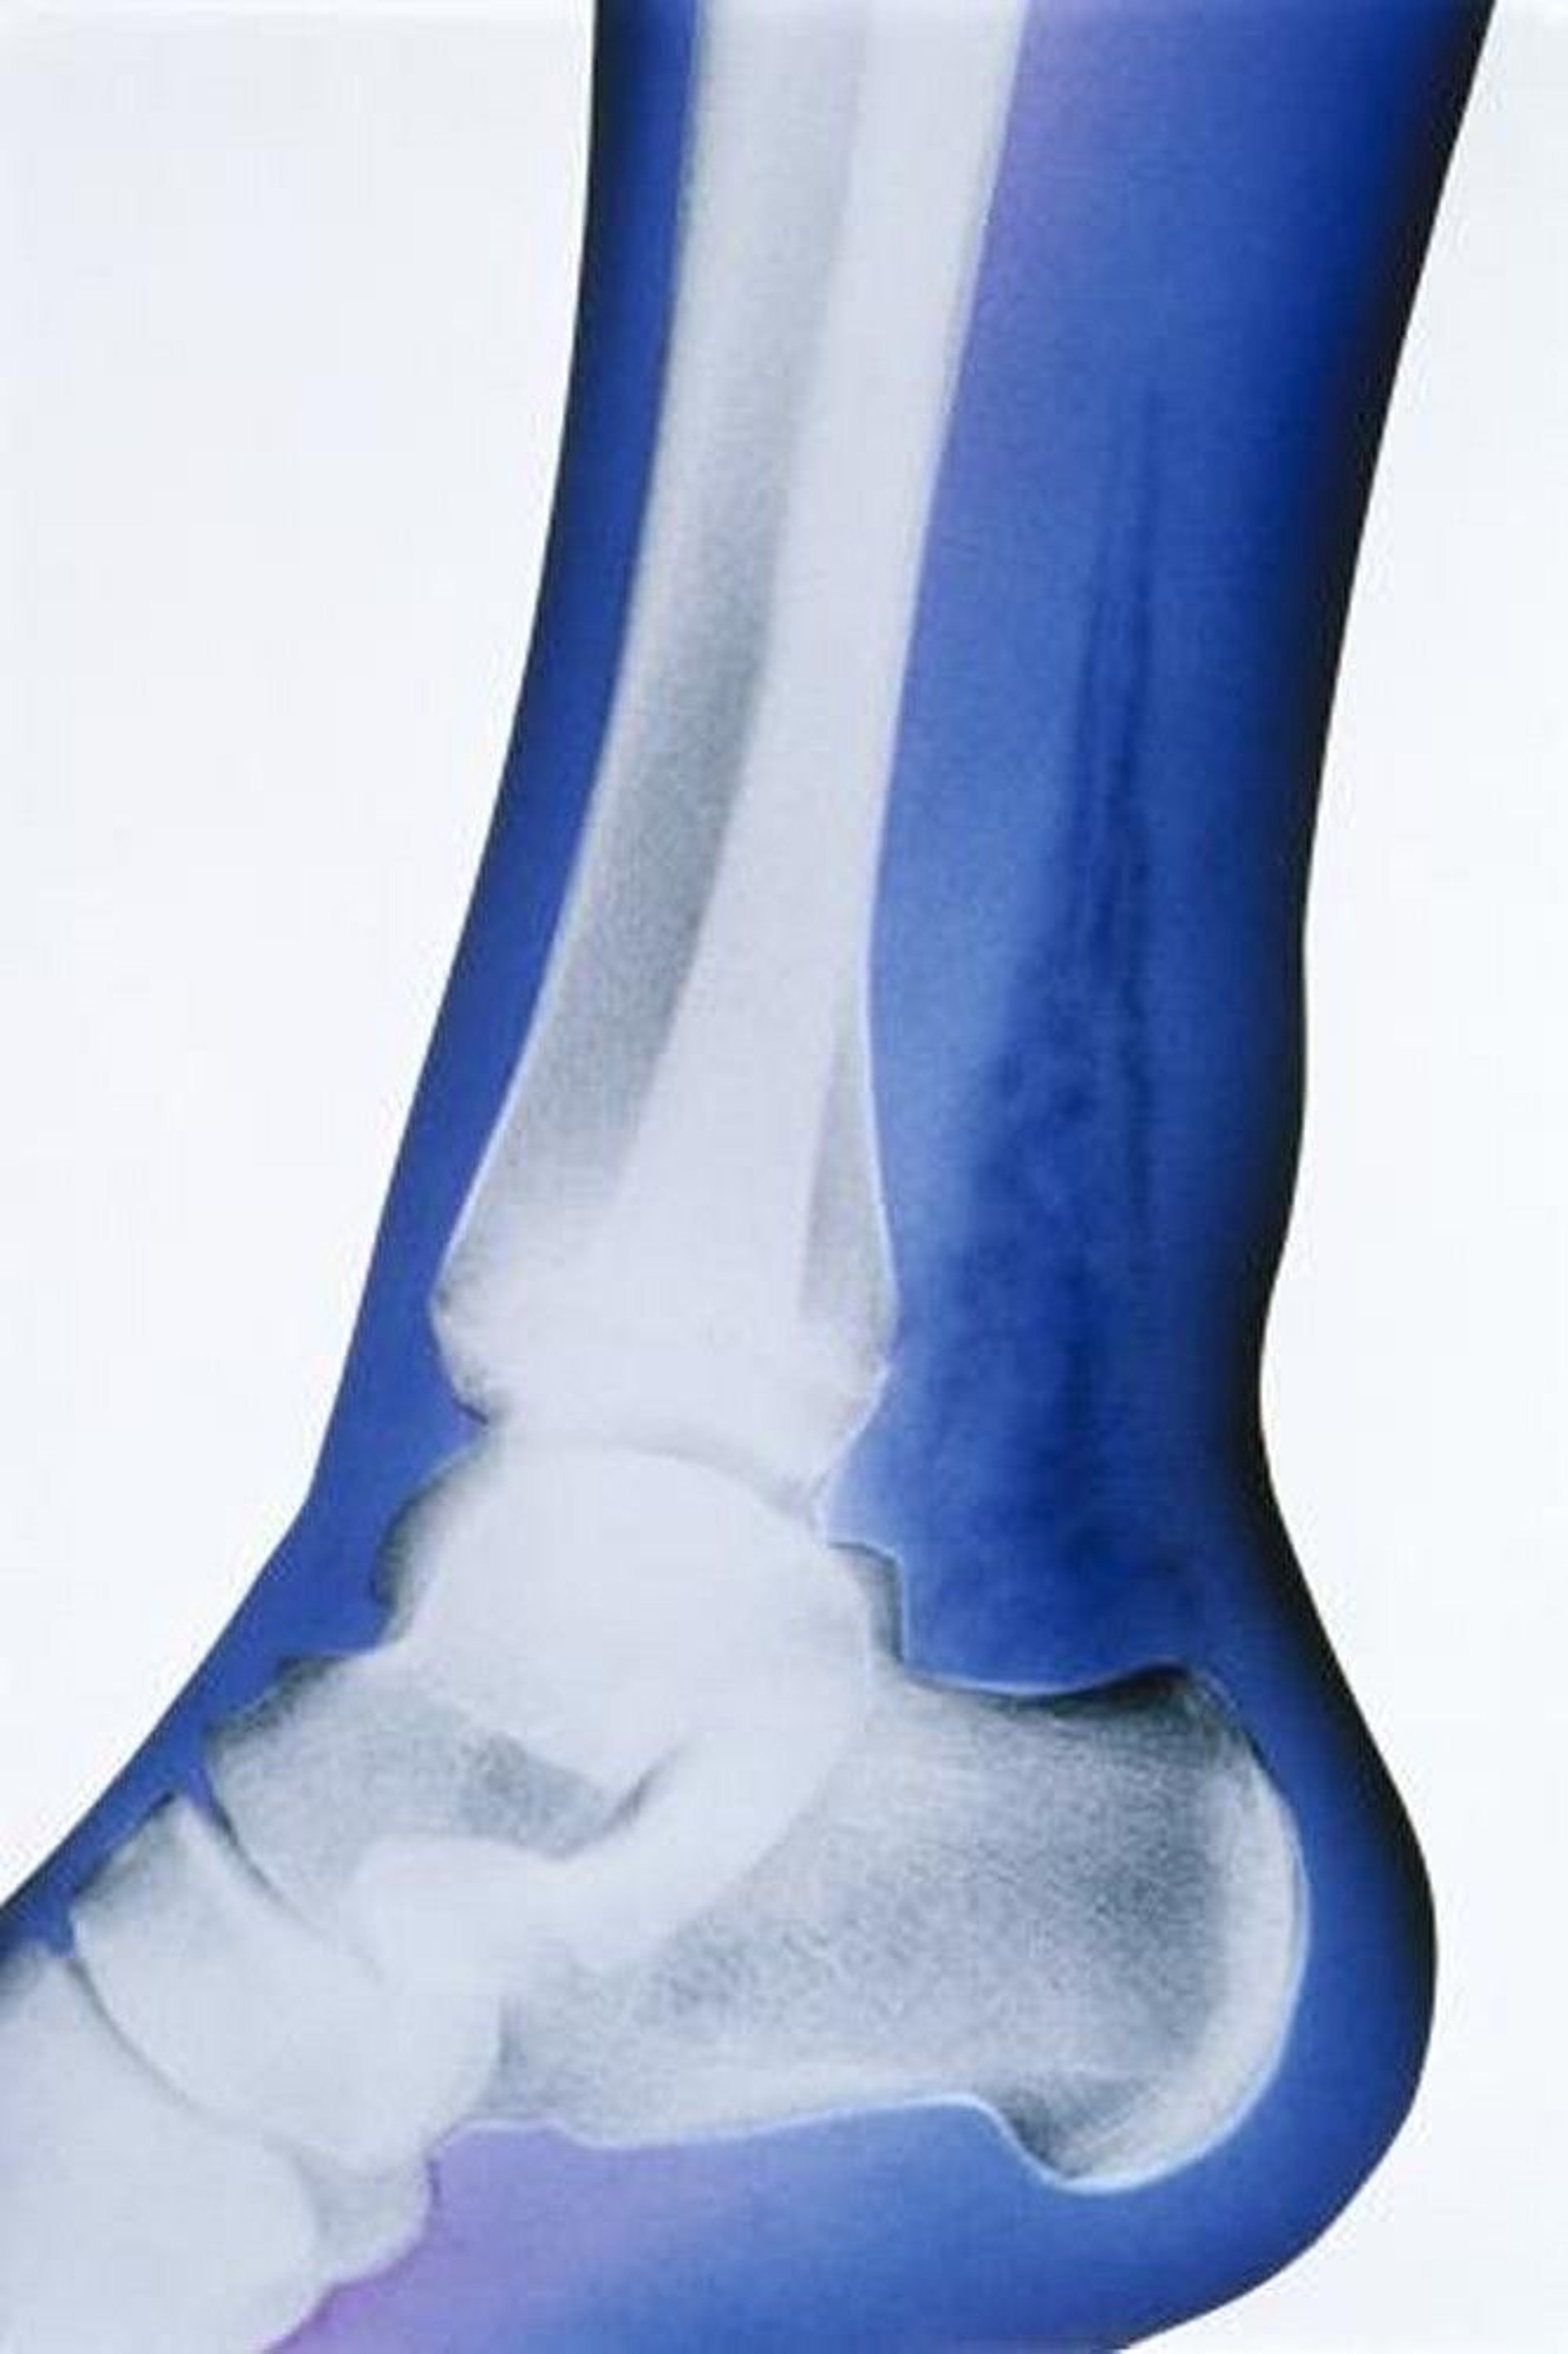

Necrotizing Subcutaneous Infection (X-Ray)

In this artificially colored x-ray, the salient finding is the presence of soft-tissue gas, indicated by the highly radiolucent densities superior to the calcaneus and posterior to the tibia and fibula.